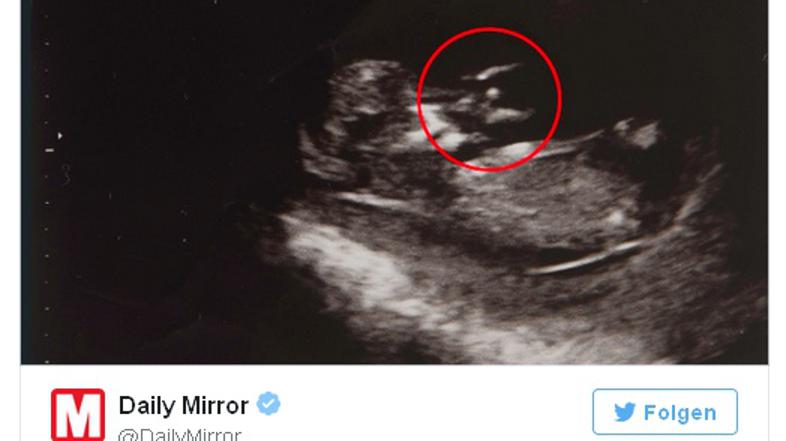

Angel na ultrazvoku?

Britanka Jennifer Holman je prepričana, da je na ultrazvočnem posnetku angel.

Veselje ob tretji nosečnosti je bilo zaradi preteklih izkušenj zato razumljivo manjše, kot pri prvih dveh. Nato pa je v 16. tednu nosečnosti na ultrazvočnem posnetku zagledala nekaj, kar ji je povrnilo upanje – angela. Nanj jo je sicer opozorila mama.

Tudi ko so zdravniki odkrili, da se je popkovina ovila okoli otrokovega vratu, Jennifer ni izgubila upanja, saj je bila prepričana, da ju varuje angel varuh. Porod je bil zelo dramatičen, saj je otrok zamujal na svet, in to celih 14 dni. Zaradi popkovine okoli vratu je postajal otrokov srčni utrip vedno šibkejši, zato so se zdravniki odločili za carski rez in malemu Josephu rešili življenje.